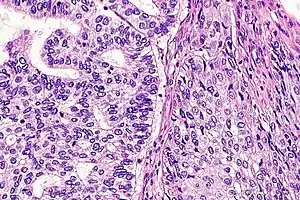

Micrograph of adenosquamous carcinoma of the pancreas.

Light microscopy shows a combination of gland-like cells and squamous epithelial cells.[4] On immunohistochemistry, it is typically positive for CK5/6, CK7 and p63, and negative for CK20, p16 and p53. On genetic testing, KRAS and p53 are typically altered.[4]